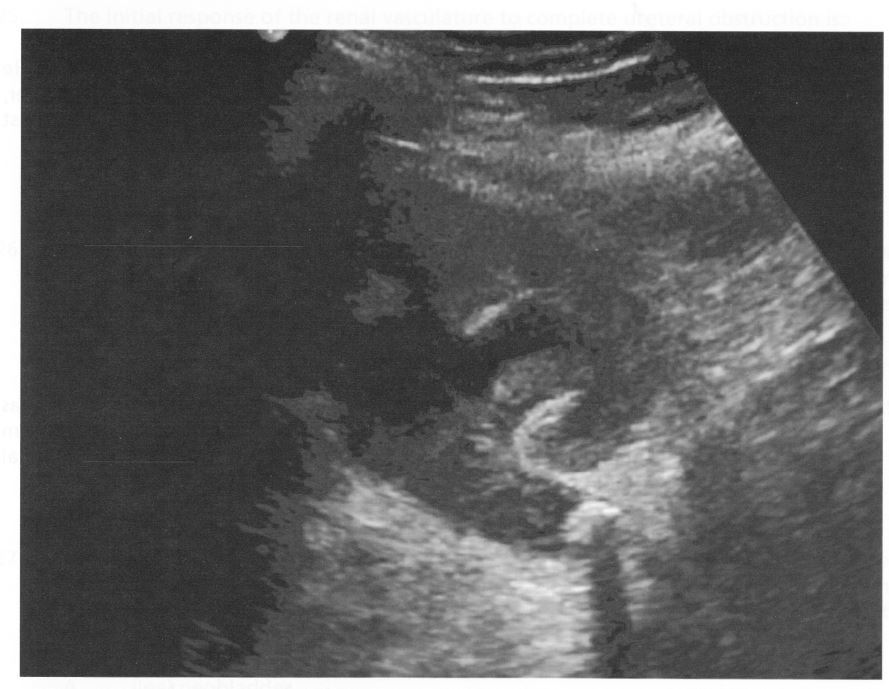

A 17-year-old boy with spina bifida has a two-week history of fever and vague abdominal pain. He has a prior bladder augmentation, appendicovesicostomy, bladder neck sling, and bilateral cross-trigonal ureteral reimplantation. Renal ultrasound is shown. The next step is antibiotics and:

D

This boy has a large proximal uretera l stone with acoustic shadowing and debris in the collecting system on ultrasound. With the size of the stone and duration of symptoms, the stone is unlikely to pass spontaneously and will require surgical intervention. The previous reconstructive procedure (bladder neck sling, cross trigonal reimplant, and Mitrofanoff) makes bladder/uretera l access difficult, and the small ureteral stent may become occluded from mucus in bladder from the bladder augmentation. The best way to remove the stone will likely be through the percutaneous approach, and in the face of fever, an initial drainage procedure with a nephrostomy tube will allow a period of antibiotic therapy and access for percutaneous removal. The patient is unlikely to have a secondary bladder perforation, making CT cystogram not helpful.